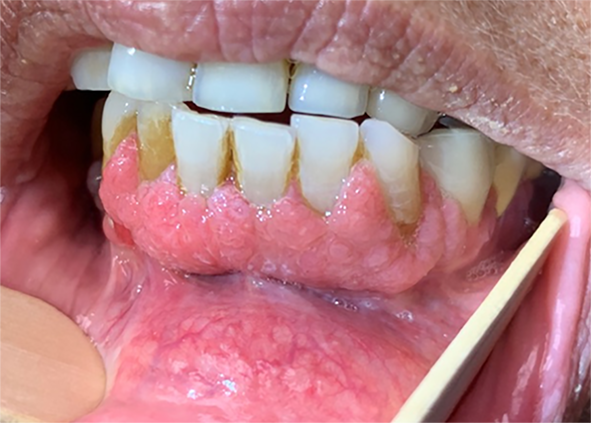

Figure 1 shows a representative clinical image of a typical verruciform, somewhat textured, and relatively homogenous leukoplakia, affecting the lower gum. On histology (Fig. 2), the squamous epithelium shows both exophytic and endophytic proliferative features, forming a bulky lesion with numerous tongue- or finger-like epithelial projections, focally coalescing, extending broadly in a pushing and sawtooth appearance into the underlying stroma with displacement and splaying bundles of fibrous connective tissue. The bulky tissue projected into the oral cavity lumen, but with broad rete rather than in a verrucous configuration, showing a much more rounded and cauliflower-like appearance. Hyperkeratosis and parakeratosis were present, but there were no church spire-type features or areas of parakeratotic crypting. Mitoses were not increased above the basal/parabasal layers. There was focal paradoxical maturation, with squamous eddies at the basal zone, associated with acute and chronic inflammatory cells. Significant pleomorphism was absent. The overall morphologic features of “barnaculate” carcinoma with a “stuck-on” appearance were present, lacking well developed features of either VC or CSCC. The other cases all demonstrated similar histologic features and thus are not further illustrated.

Fig. 1

Verrucous hyperplasia was noted to predominantly involve bilateral mandibular alveolus and be centered in the symphysis and para-symphyseal regions. The area seemed somewhat textured throughout but homogenous without specific standout regions. (Patient 1)